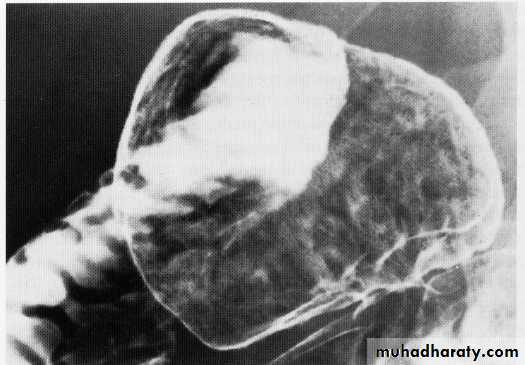

Benign gastric tumor